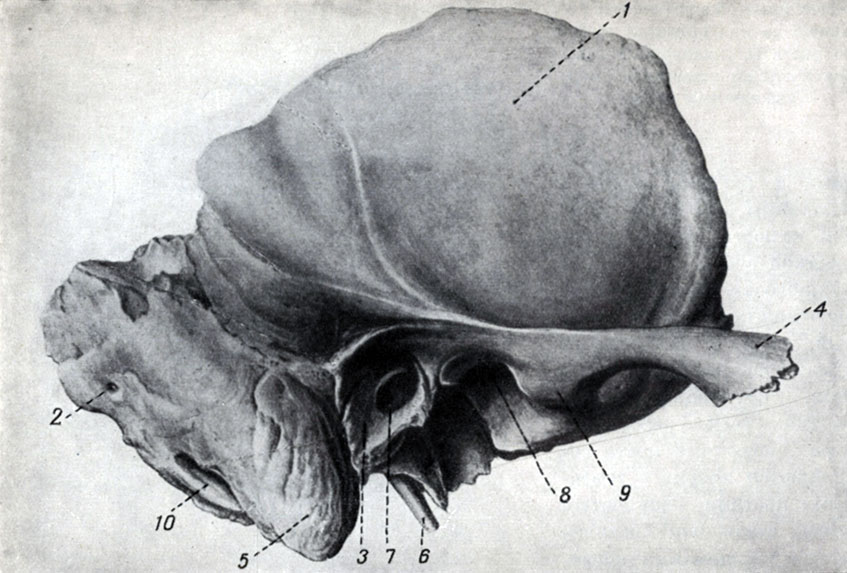

Анатомия сосцевидного отростка